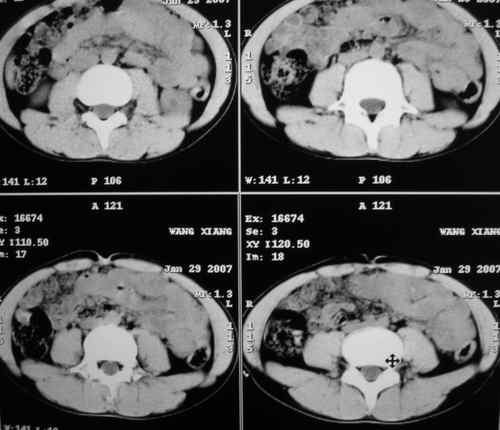

m 15y 外院b超发现左肾包块,遂来ct检查。

左肾外形明显小于右肾,左肾中上极后侧可见一等密度影,与肾分解不清,肾盂肾盏无扩张,先考虑:左肾发育不良,建议强化除外占位

左肾外形明显小于右肾,左肾中上极后侧可见一等低密度影,与肾分解不清,肾盂肾盏无扩张,先考虑:左肾发育不良,平滑肌脂肪瘤待排除。